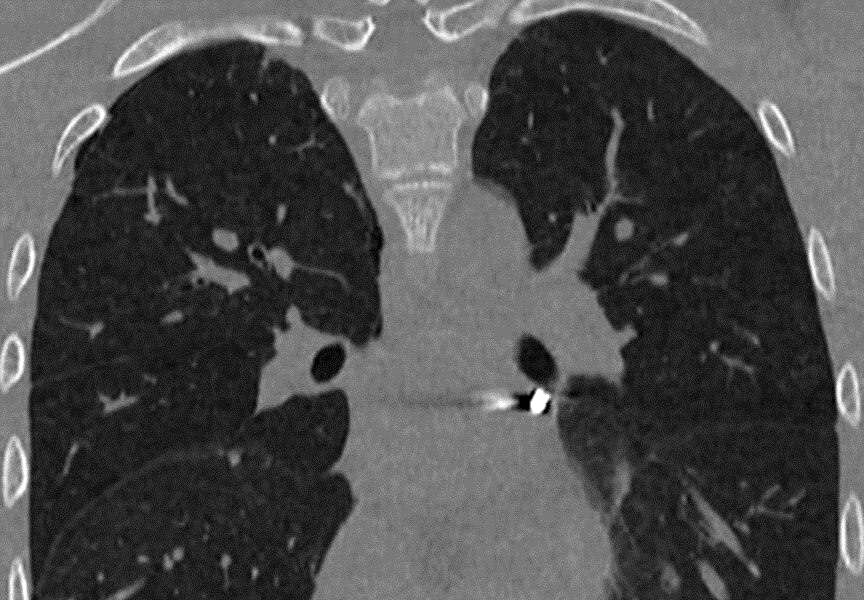

«Инородное тело мигрировало в опаснейшую зону — между легочными венами у задней поверхности предсердия. Мы выполнили малоинвазивную операцию со вскрытием перикарда, работая буквально в миллиметрах от жизненно важных структур», — рассказал заведующий отделением детской хирургии № 2 Никита Степаненко.